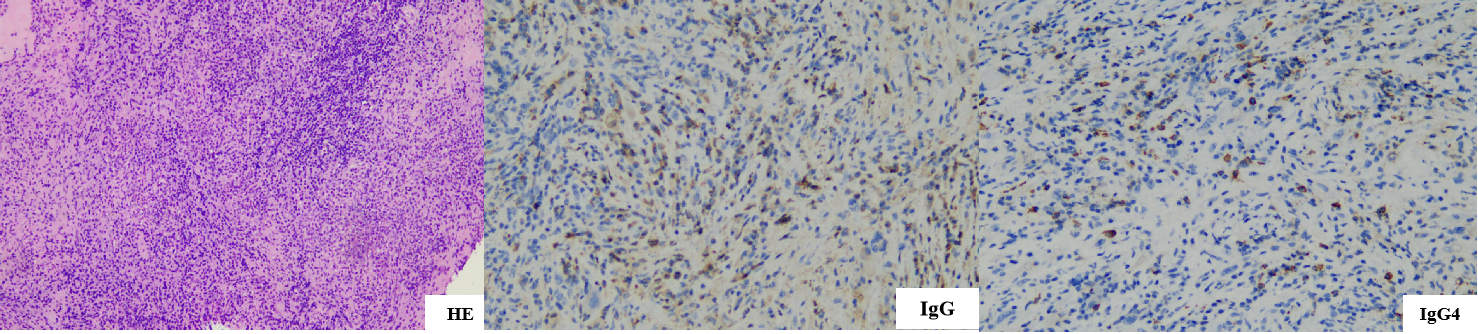

此后所有的诊断和治疗工作都在绿色通道中以最快的速度完成。病理科加急加做IgG4/IgG比值并最短时间内发布报告:可见大量浆细胞、淋巴细胞浸润及中性粒细胞浸润,纤维组织增生,免疫组化:IgG4/IgG比例约40%,热区IgG4阳性细胞数约20个/HPF,倾向IgG4相关硬化性疾病(图3)。终于在大家齐心协力下拨云见日,看清了这一罕见病的面目。而此时,及时的激素冲击治疗已使患者的视力和听力均迅速好转,并转至免疫风湿科继续治疗。